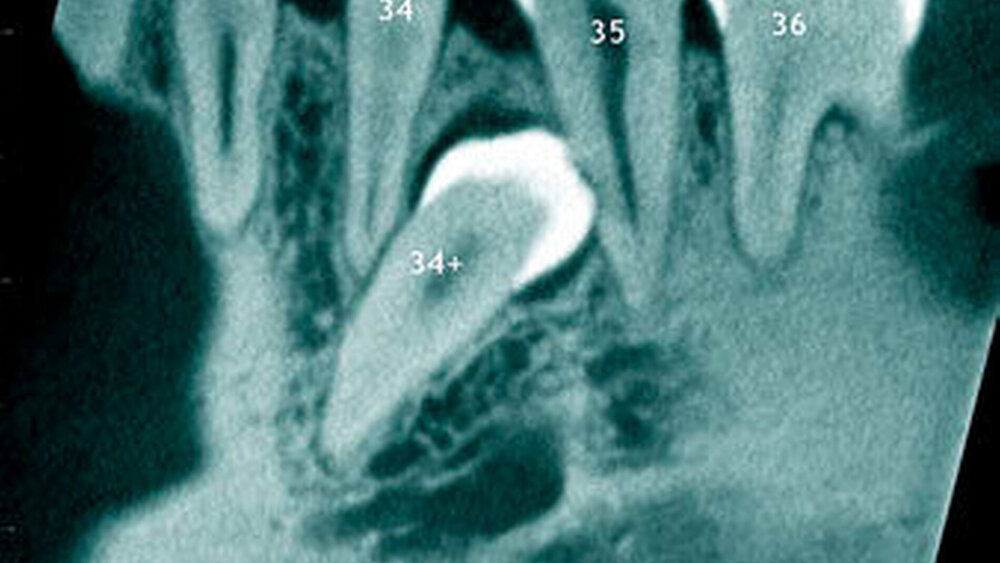

In einer aktuellen Arbeit berichteten Mossaz und Mitarbeiter (2014) über eine relativ hohe Prävalenz (22,8 Prozent) der Wurzel- resorptionen an benachbarten Zähnen, wobei besonders häufig überzählige Prämolaren zu Resorptionen führen (Abbildung 18). Für die Beurteilung der Wurzelresorptionen wurden digitale Volumentomografie (DVT) der Patienten herangezogen. In einer Studie aus China, welche ebenfalls DVT-Bilder beurteilte, wurde über eine deutlich geringere Häufigkeit von Wurzelresorptionen (1,6 Prozent) berichtet [Liu et al., 2007]. Im Gegensatz zu den Daten aus der Schweiz war Diagnose und Bewertung von Wurzelresorptionen kein primäres Ziel dieser Studie und es wurde auch keine Information über das Ausmaß der Resorptionen gegeben.

Daher könnte diese Studie leichte oder mäßige Wurzelresorptionen nicht eingeschlossen haben, was zumindest einen Teil des doch deutlichen Unterschieds in den Prozentsätzen erklären würde. Studien, welche Panoramaschichtaufnahmen zur Diagnose von Wurzelresorptionen heranziehen, berichten über Resorptionsraten zwischen 4,7 Prozent [Gündüz et al., 2008] und 7,6 Prozent [Hyun et al., 2009]. Tyrologou und Mitarbeiter (2005) berichteten sogar, dass keine Resorption im untersuchten Patientengut vorhanden waren. Allerdings wurden in dieser Studien nur Mesiodentes beurteilt, wo Wurzelresorption benachbarter Zähne eher selten vorkommen [Mossaz et al., 2014]. Generell lässt sich festhalten, dass zweidimensionale Röntgenaufnahmen für die Diagnose von Wurzelresorptionen eher ungenau sind und diese so in bis zu 50 Prozent der Fälle übersehen werden [Ericson Kurol, 1987, Heimisdottir et al., 2005; Botticelli et al., 2011; Alqerban et al., 2011a].